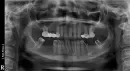

Зуб №5 на нижней челюсти. Был штифт в зубе, 10 лет зуб не беспокоил. Врач настояла на том, чтобы удалить штифт и перепломбировать зуб для дальнейшего протезирования. Врач сделала анестезию септонесетом, расширила канал и влила метапасту, которая вылезла за пределы зубных корней в костную ткань. После того, как прошла анестезия, онемение нижней губы и соседних зубов не прошло. Врач уверяла, что пломбировочный материал рассосется и не назначала никакого лечения. Прошел год, губа и рядом зубы в таком же состоянии. Сделала свежий снимок. Объясните, пожалуйста, что делать с этим пломбировочным материалом, возможно ли его убрать без хирургического вмешательства и нужно ли беспокоиться, если оставить его там?

Крайняя безграмотность и халатность врача. Извините, существует некая врачебная этика, при которой мы не обсуждаем врачебные ошибки, но это просто крайний непрофессионализм и нанесение вреда. Онемение не пройдет, так как силлер (пломбировочный материал) лежит на канале и отсюда онемение. Иногда при лечении периодонтита (при котором верхушка обычно размягчена) кальций или метапаста выходит за верхушку зуба, в этом случае это не страшно, она рассасывается за полгода. Но в вашем случае необходимо хирургическое вмешательство и желательно обратиться в ЧЛХ. Извините, что приходится вас расстраивать, но я обязан вас предостеречь и дать точные рекомендации.

• Если онемение не проходит более чем год, то ничто уже, что касается консервативных методов, вам не поможет. Да и хирургическое вмешательство рекомендую провести исключительно в ЧЛХ, чтобы избежать проблем, так как мы имеем дело с нижне-челюстнолицевым каналом (нервом). Обратитесь на очную консультацию и не переживайте, с лицом ничего не случится!